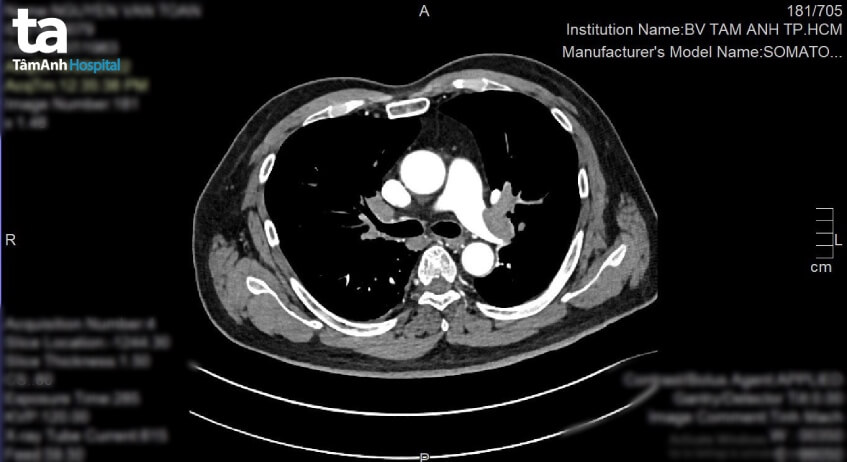

10h30 cùng ngày, xe cấp cứu từ Campuchia về đến khoa Cấp cứu, BVĐK Tâm Anh TP.HCM. Bác sĩ CKI Đoàn Quốc Anh tiếp nhận ông D. trong tình trạng khó thở, vã mồ hồi, nét mặt tái xanh, huyết áp 90/70mmHg, chỉ số SpO2 (mức độ bão hòa oxy trong máu động mạch) giảm còn 89% (bình thường 95% – 100%), mạch nhanh 135 lần/phút, có khả năng suy hô hấp nặng, nguy kịch tính mạng. Nghi ngờ người bệnh bị thuyên tắc phổi, bác sĩ Quốc Anh chỉ định chụp CT-scan. Kết quả ghi nhận người bệnh bị thuyên tắc phổi do huyết khối cấp gây tắc gần hoàn toàn động mạch phổi phải, động mạch phổi trái và các nhánh động mạch phổi 2 bên.